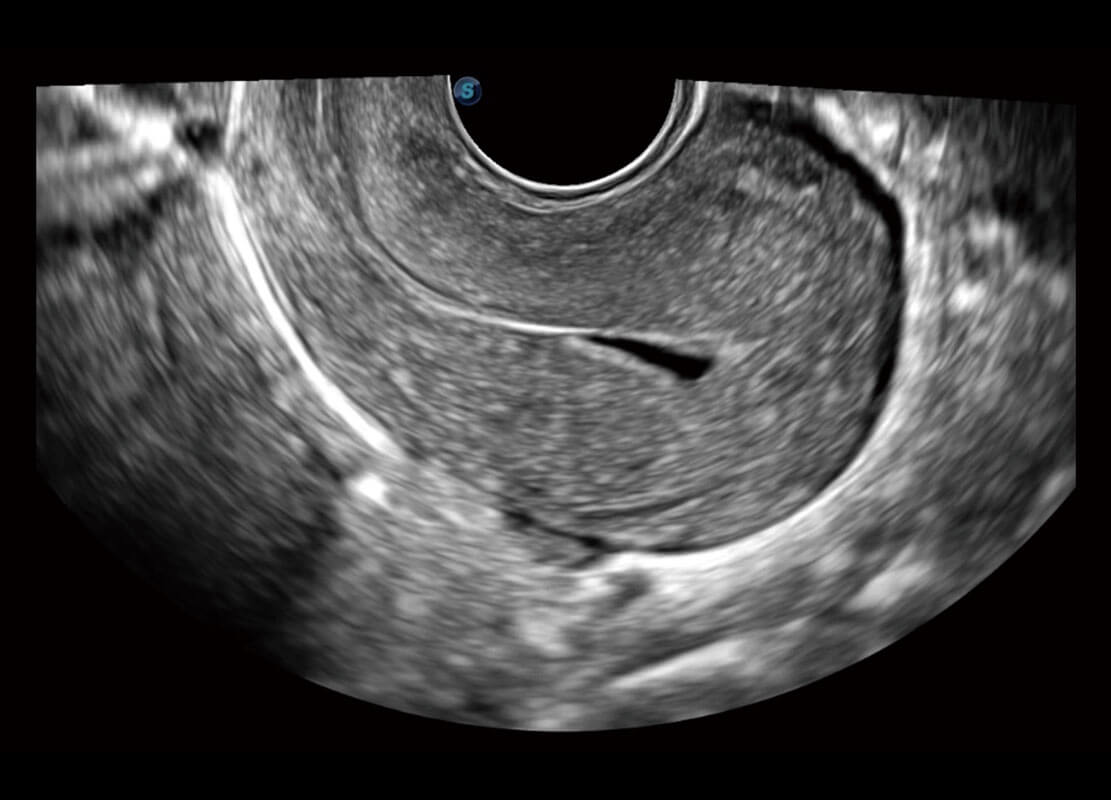

腔内妇科-卵巢

腔内三维-宫内节育器

腔内三维-光影成像